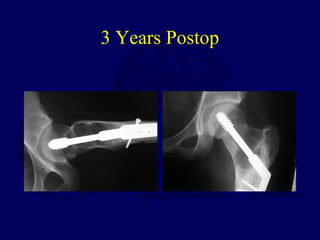

14 yo female - fell walking across front yard

3 months of left hip pain - Motrin

referred for “path fx through Ewing’s sarcoma”

Dx -polyostotic fibrous dysplasia

3 Years Postop

Fibrous Dysplasia